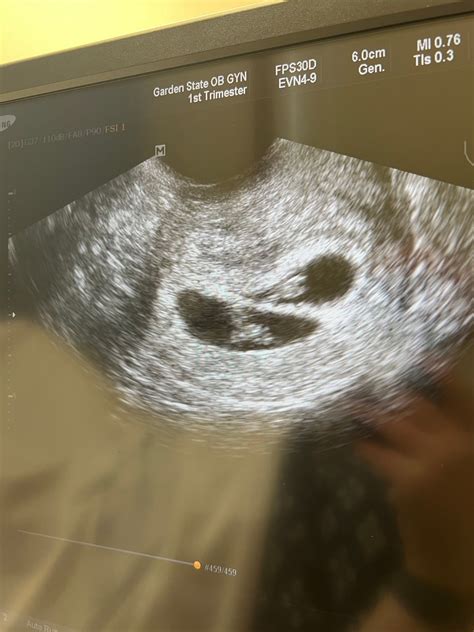

7 Week Ultrasound

The 7 week ultrasound is typically performed transvaginally, which involves inserting a probe into the vagina to get a clearer image of the uterus and the developing embryo. This method is particularly useful in the early stages of pregnancy when the embryo is still very small. The ultrasound can detect the gestational sac, yolk sac, and fetal pole, which are essential indicators of a healthy pregnancy.

During this scan, the sonographer will look for several key indicators:

• The gestational sac: A fluid-filled structure that houses the embryo.

• The yolk sac: A small sac that provides essential nutrients to the embryo.

• The fetal pole: The earliest visible part of the embryo, which will eventually develop into the fetus.

• Heartbeat: Although it may be too early to detect a heartbeat at 7 weeks, some advanced ultrasound machines can pick up the fetal heartbeat around this time.

• 7 week ultrasound twins